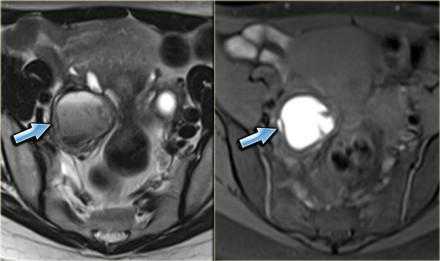

КТ- и МР-признаки эндометриоза брюшной стенки не являются специфичными: и при КТ, и при МРТ обнаруживается солидное образование в брюшной стенке, накапливающее контраст.

Эндометриоз передней брюшной стенки: фото МРТ. Очаг поражения обладает интенсивностью сигнала, сравнимой с мышцами, содержит также мелкие гиперинтенсивные очажки, отображающие расширенные эндометриальные железы. Они характеризуются слегка более интенсивным сигналом по сравнению с мышцами на Т1 ВИ с жироподавлением (стрелка)

На аксиальной Т2 ВИ МР-томограмме продемонстрирован другой пример поражения брюшной стенки.